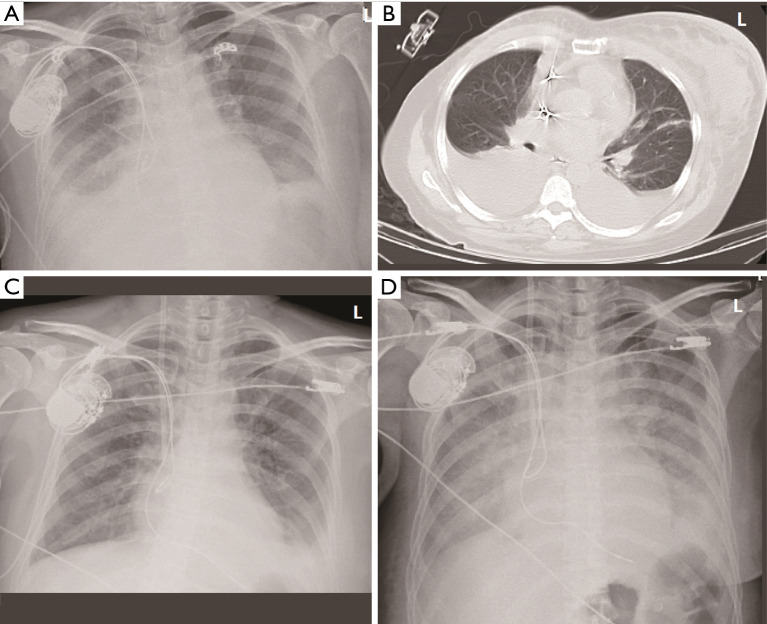

Case description: We describe a 45-year-old female who developed metastatic SBC 18 years after curative HL treatment. The diagnosis of TMA was established on the basis of thrombocytopenia, hemolytic anemia (elevated lactate dehydrogenase, low haptoglobin, and a reticulocyte count of 5.72%), and multi-organ dysfunction, following the exclusion of thrombotic thrombocytopenic purpura and Shiga toxin-producing Escherichia coli (STEC)-hemolytic uremic syndrome. In this case, the multifactorial etiology-stemming from both paraneoplastic endothelial injury and chemotherapy-induced toxicity-complicated the clinical picture. Despite aggressive supportive measures, including plasma exchange and antibiotics, the patient's condition rapidly deteriorated, culminating in fatal cerebral hemorrhage.